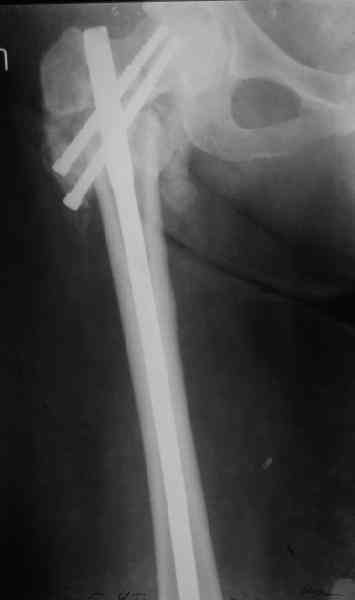

Уважаемые коллеги, хотелось бы услышать ваше мнение по следующему случаю: Относительно молодая женщина(39 лет), поступила в клинику в марте 2005 года, через 3 месяца после травмы с Неправильно срастающимся поперечным межвертельным переломом правого бедра. Был выполнен закрытый интрамедуллярный остеосинтез правого бедра канальным реконструкционным стержнем ChM. Ожидали бОльших проблем на операции, результату обрадовались. Как оказалось, зря. Сращение наступило через 3,5 месяца после операции. В ноябре 2005 года произошел перелом шейки бедра и винтов в ней. В апреле 2006 импланты были удалены. В приложении фото и рентгенограммы больной. Сопутствует ожирение 4 ст. (при росте 168 см., вес больной 140кг.), сахарный диабет II тип. Имеется медиальная неустойчивость коленного и голеностопного суставов, при нагрузке колено вальгируется на 15-20 градусов. Вопросы: 1.Целесообразность эндопротезирования (в настоящий момент передвигается на ходунках)? 2.Если ответ на первый вопрос-да, то каким протезом? 3. С какими проблемами можем столкнуться во время и после операции? Заранее благодарен за ответы. Салават Салаватов, Екатеринбург